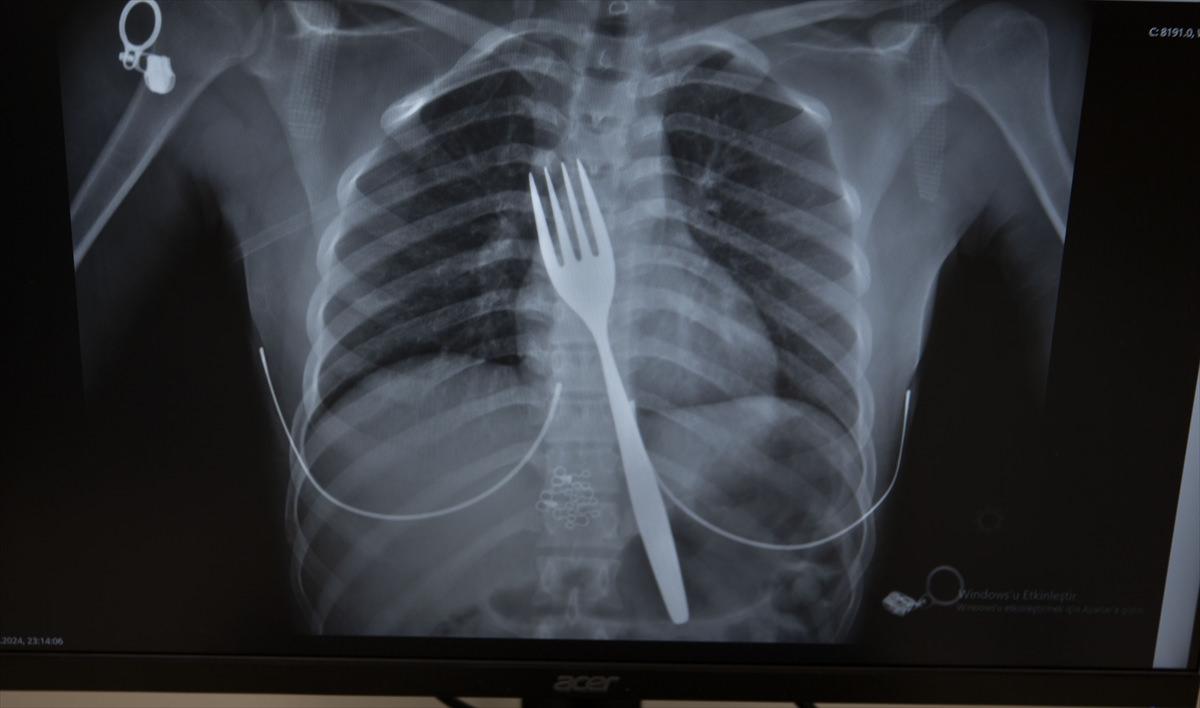

Burada röntgeni çekilen hastanın yemek borusunda 18 santimlik çatal olduğu tespit edildi.

Uzmanlar endoskopi yaparak çatalı ağızdan çıkarmayı denedi. Fakat yemek ve soluk borusuna zarar verme ihtimalinden dolayı midenin kesilerek çatalın çıkarılmasına karar verildi.

Vakayı ilk duyduğunda şaşırdığını anlatan Edizsoy, "Büyük bir çatalın tamamen yutulması şeklinde ortaya çıkan bu vakayı ilk duyduğumda doğru olmadığını düşündüm. Hasta 18 yaşında ve yabancı uyrukluydu. Türkçesi biraz zayıf olduğu için belki de yanlış anlaşılmalar olabileceğini düşündük. Ama hastanın filmini çektiğimizde gerçekten bir çatalın yemek borusunda olduğunu gördük." dedi.

"Biz en çok bu yüzden tedirgin olduk. Ama ciddi bir yaralanma olmadığını da yapılan endoskopiyle gördük. Endoskopi ile çıkarılamadı çünkü oldukça büyüktü ve endoskopik aletler için uygun değildi. Bu büyük bir yemek çatalı olduğu için kendi ağırlığı da var. Bir çivi gibi, iğne gibi tutulup çekilemiyor. Bundan dolayı karında yapılan kesi ile mideye ulaşıp midenin içinden bunu çıkarmak şeklinde bir strateji izledik. Yaptığımız bu ameliyatla da bu çatalı oradan çıkarabildik."